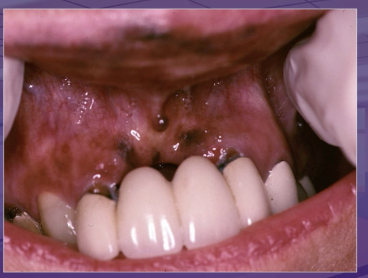

what is the dx

amalgam tattoo

melanotic macule

melanoma

melanocytic nevus